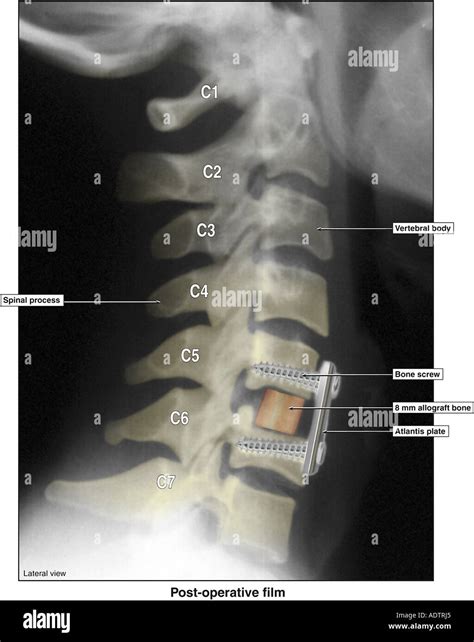

• Bone Graft or Cage Placement: A bone graft or an artificial cage filled with bone graft material is placed in the disc space. This promotes fusion between the vertebrae.

• Plate and Screw Fixation: A metal plate with screws is often used to stabilize the vertebrae and ensure proper alignment during the healing process.

• anterior cervical fusion xray